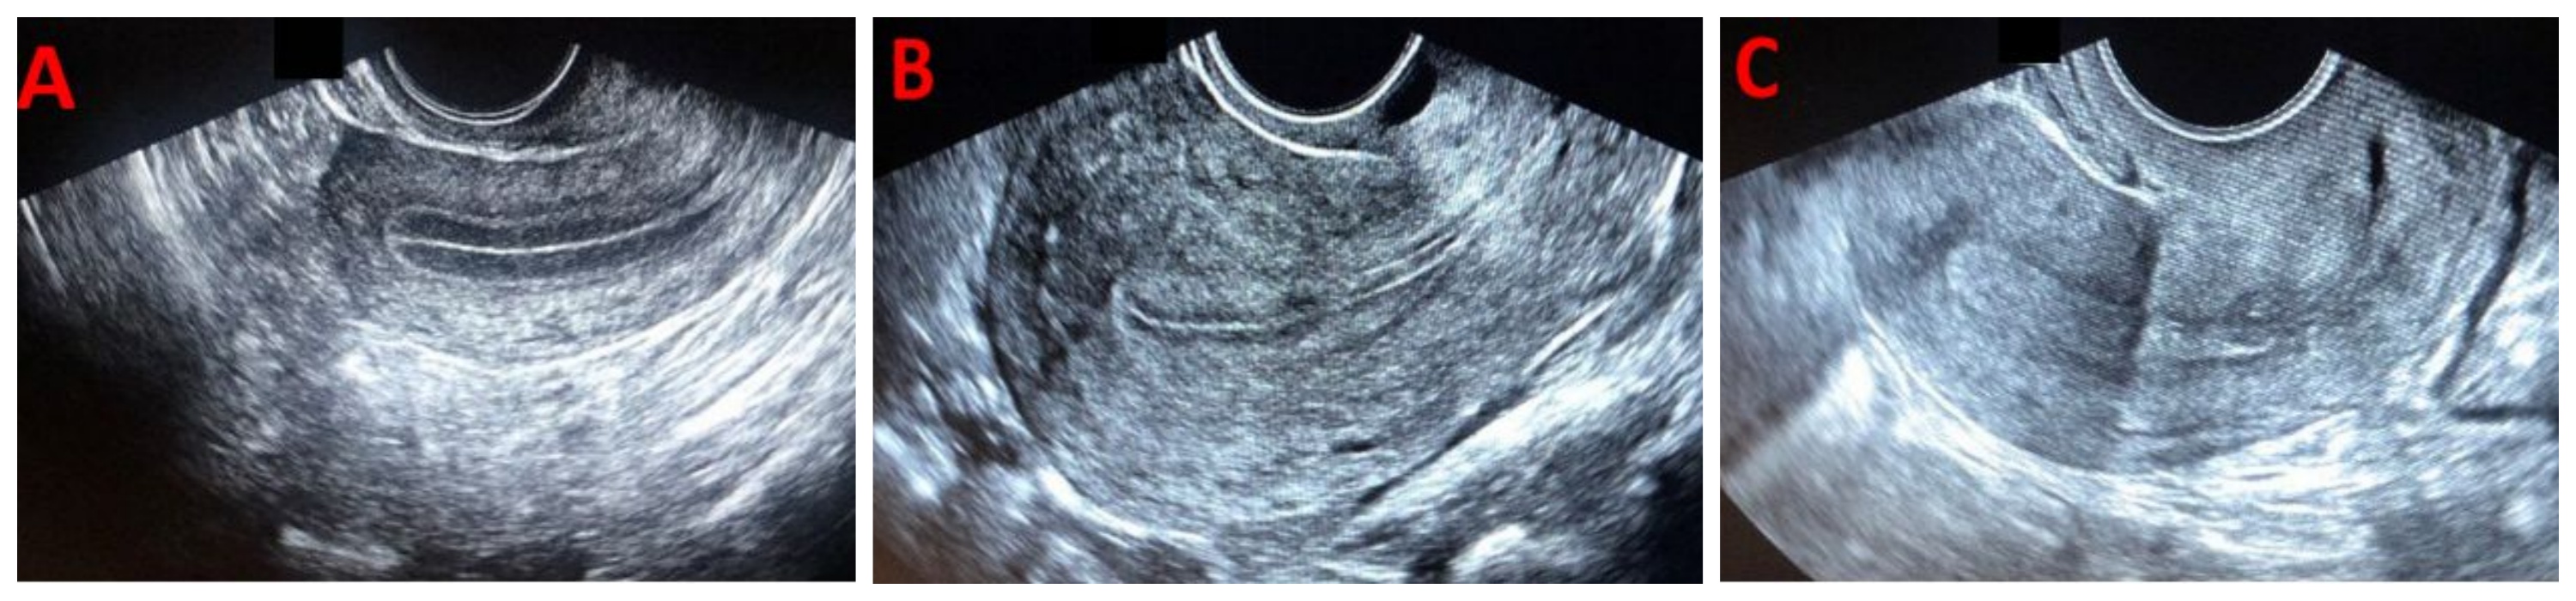

B超下看内膜,分ABC型。A型是典型的“三线征”,内膜功能层和基底层分界清晰,质地松软,是着床的理想状态。B型次之,C型差,内膜回声增强、质地偏硬,胚胎不容易钻进去。